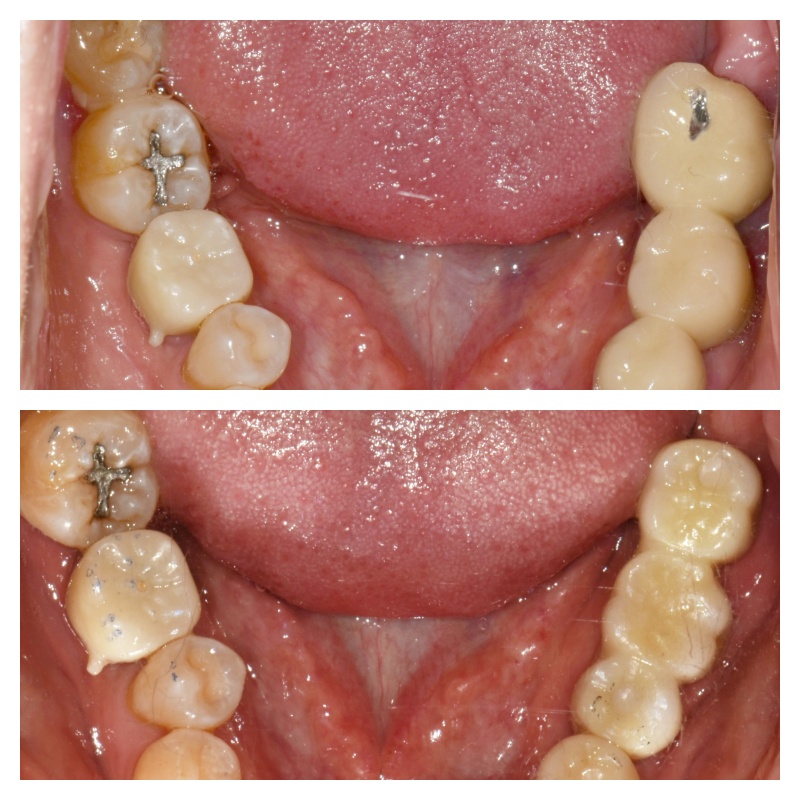

치료 진행과 결과

​위와 같이 임플란트 치료가 진행되었습니다. 상악 어금니는 상악동 거상술을 동반하여 뼈이식 임플란트를 식립하였고

​아래턱뼈는 그 양이 충분했기에 따로 뼈이식이 필요 없었습니다. ​

그리고 앞니 임플란트까지 잘 심어드렸네요.

어금니를 든든하게 만들어 드렸고 어금니와 앞니가 상호 보호하는 역할을 수행할 수 있도록 보철 과정을 잘 진행했습니다.

​6개월 검진 오셨는데 불편한 점 없이 잘 쓰고 있다고 고맙다고 인사 전해주셨네요.^^